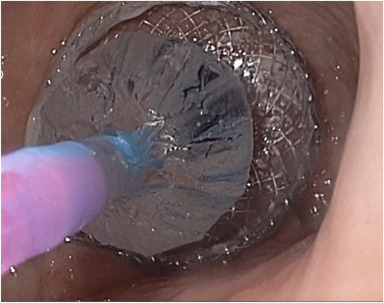

Gainey et al perform "Single-session endoscopic retrograde cholangiopancreatography and endoscopic ultrasound—guided gallbladder drainage for management of biliary obstruction and gallbladder disease." https://t.co/fZiSNeKRGp @cgaineyMD @kellyhathornMD @endoTX @trieuMD

VideoGIE Editor's Choice: “EUS-directed transgastric PEG for long-term enteral feeding in patients with Roux-en-Y gastric bypass anatomy” by Christina S. Gainey and Todd H. Baron. https://t.co/ccXmuXCPeZ #GITwitter @CGaineyMD @EndoTx

Just posted on the Endoscopedia blog: "EUS-directed transgastric PEG for long-term enteral feeding in patients with Roux-en-Y gastric bypass anatomy" by Christina S. Gainey https://t.co/sYhp2mXJJa